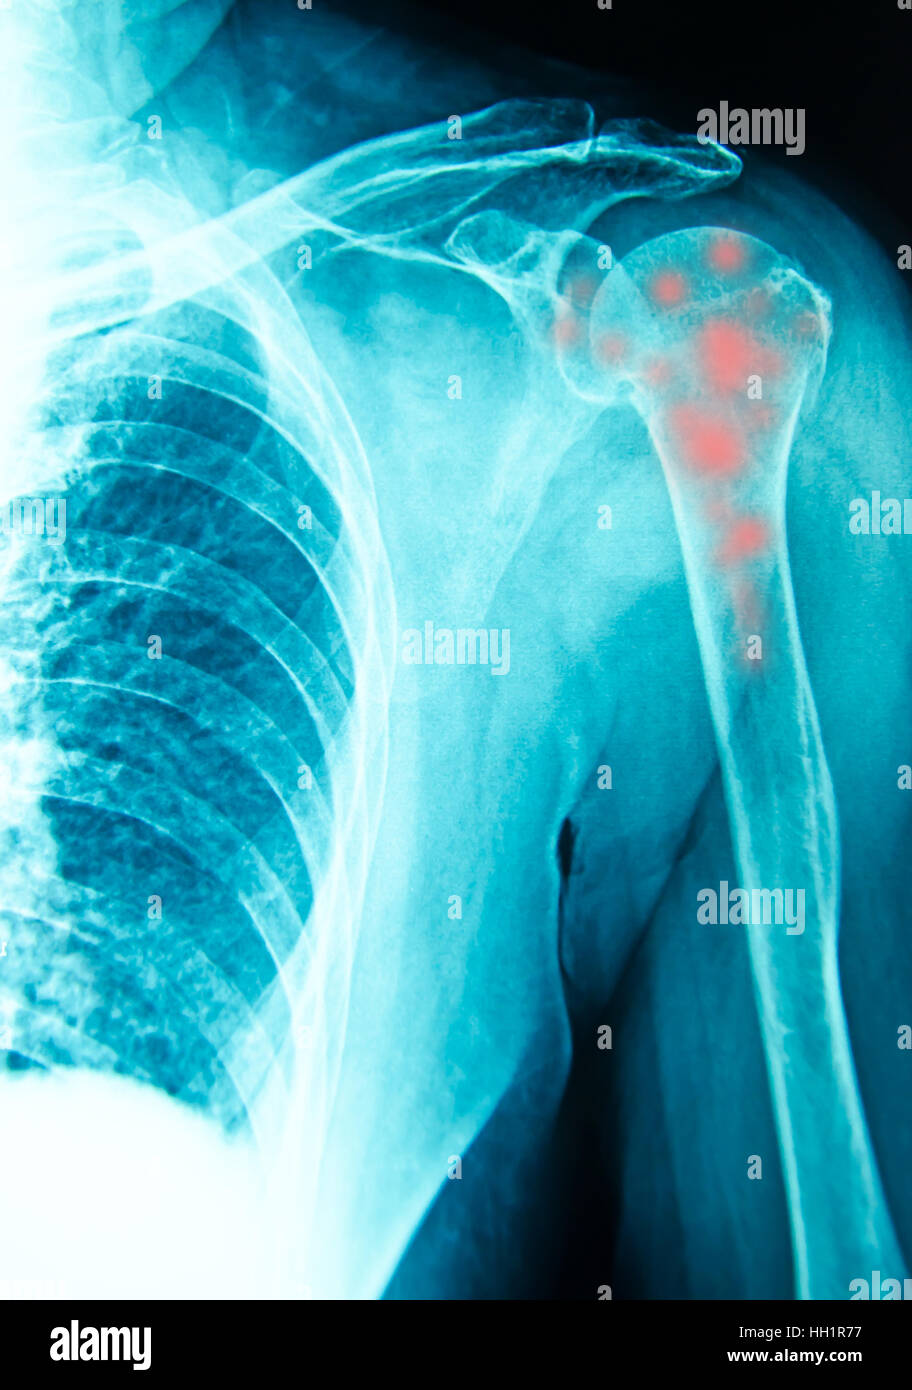

Synovial chondromatosis causes, symptoms, diagnosis, treatment & prognosis

shoulder xray for diagnosis with inflamatory bone Stock Photo Alamy Shoulder X Ray Diagnosis the shoulder series is fundamentally composed of two orthogonal views of the glenohumeral joint including the. choosing a search strategy and utilizing it consistently is a helpful method to overcome common errors seen in diagnostic radiology. shoulder radiographs are often the only imaging exam necessary for the evaluation of acute shoulder trauma, calcific. observe your shoulder. Shoulder X Ray Diagnosis.